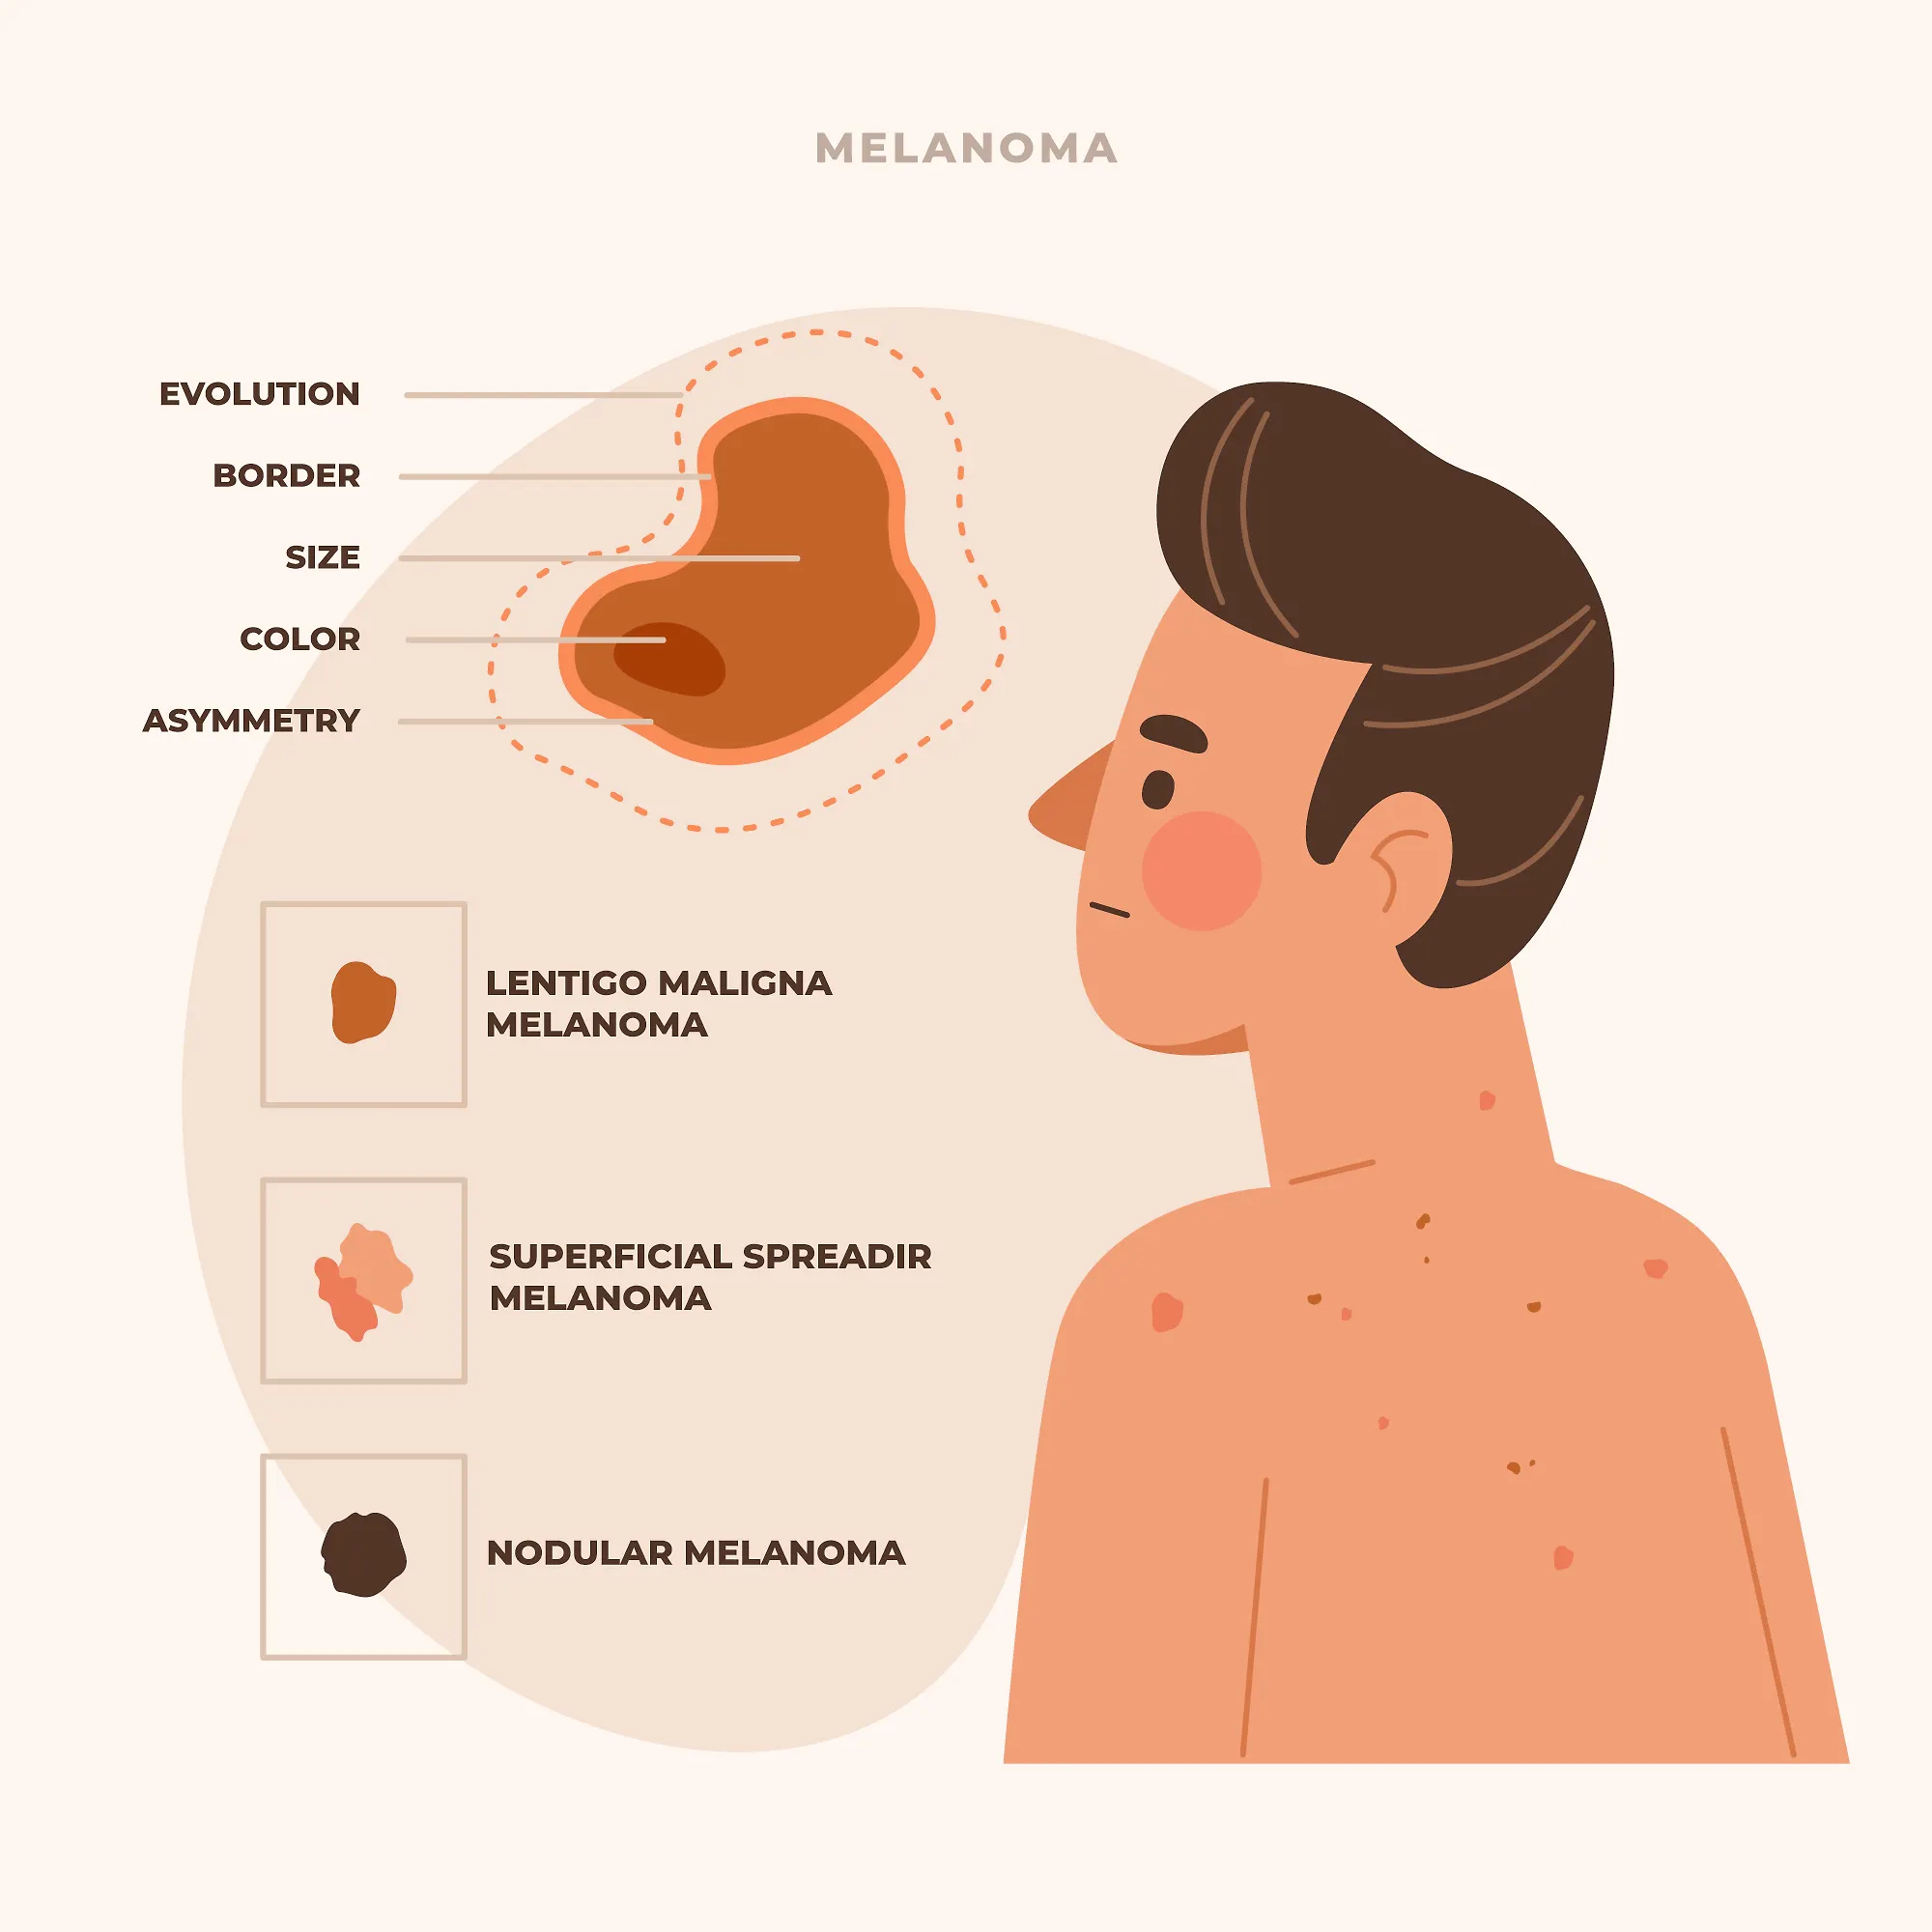

Europski dan borbe protiv melanoma - besplatni pregledi mladeža i sumnjivih promjena na karcinom kože

Zdravstvo-vijesti

15.05.2023